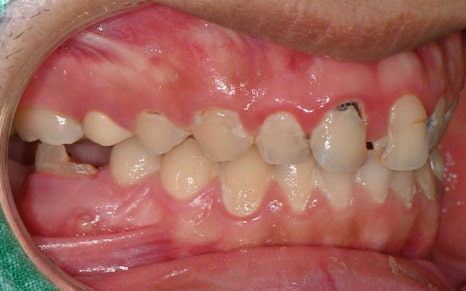

💛 초진 💛

소개해드릴 환자분은

충치가 여러 개 진행된 상태였고,

통증이 있다가 말다가 반복되어

더욱 치료 타이밍을 놓치기 쉬운 상황이었습니다.

실제로 진료기록에서도 확인되듯이

10개가 넘는 치아에 대해

신경치료(근관치료)를 받으셨고,

대부분 복잡한 염증과 신경 감염이

동반되어 있었습니다.

특히 윗니 앞니와 어금니까지

넓은 범위에 걸쳐

치료가 진행되었습니다.

치료 전 사진을 보면 웃음을 짓기 어려울 정도로

앞니에 큰 충치와 손상이 있었고,

중간중간 레진으로 채워진 부분이

심미적으로도 큰 스트레스였다고 하셨습니다.